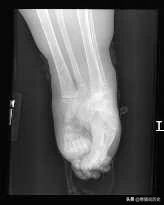

x光片

这是夏伊洛4岁时拍摄的X光片